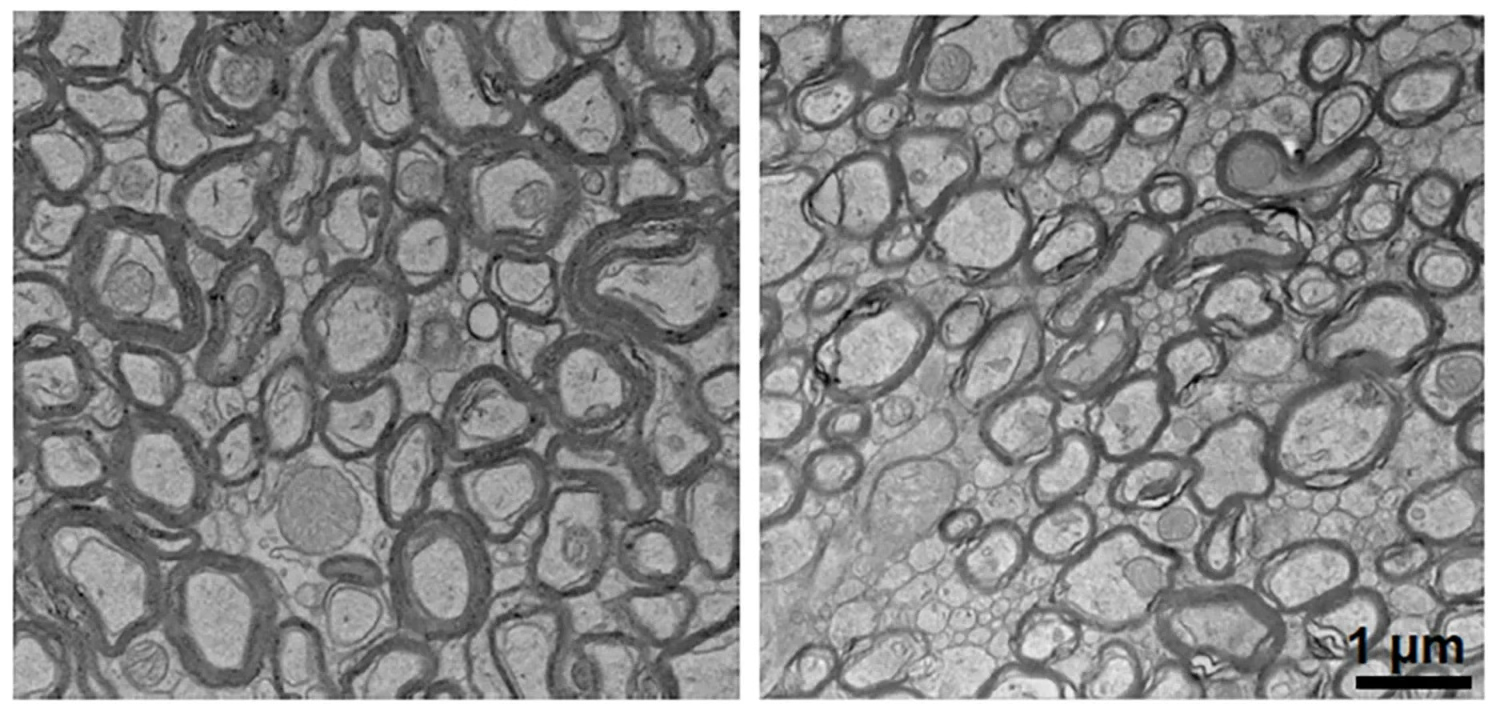

当阿尔茨海默病模型小鼠也被喂以低锂饮食时,病变更加严重:β-淀粉样蛋白沉积和磷酸化tau蛋白堆积增加;小胶质细胞被过度激活,失去了清除淀粉样蛋白的能力;突触、轴突和保护神经元的髓鞘大量丧失;认知功能和记忆能力也显著下降——这些都是阿尔茨海默病的典型特征。